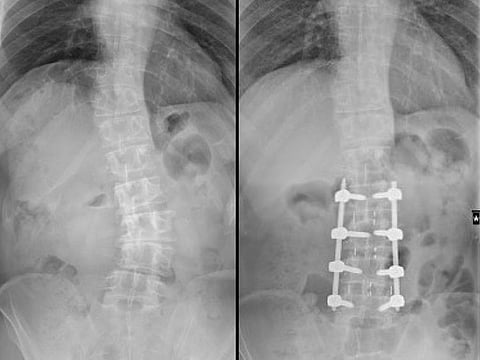

The surgery was performed by Dr Sameh Abolfotouh, orthopaedic surgeon and specialist in spine surgery at Medcare Orthopaedic and Spine Hospital in Dubai, who used the recently-introduced Oblique Lumbar Interbody Fusion (OLIF) technique to correct a 36-degree lumbar spine scoliosis due to arthritis in the patient, Abdalla Mohamed Mahmoud Sulaiman Al Ali.

In Al Ali’s case, it was a significant deformity of more than 36 degrees of the lumbar spine with severe foraminal stenosis, he explained.

According to Dr Abolfotouh, the OLIF surgery approach accesses the lower spine from the side of the patient’s belly and preserves spinal muscles. It corrects scoliosis by removing disc spaces and applying large spacers without cutting into bones or breaking the spine. This results in minimal blood loss, less postoperative pain, and faster recovery compared to conventional surgeries that enter from the back, said Dr Abolfotouh.